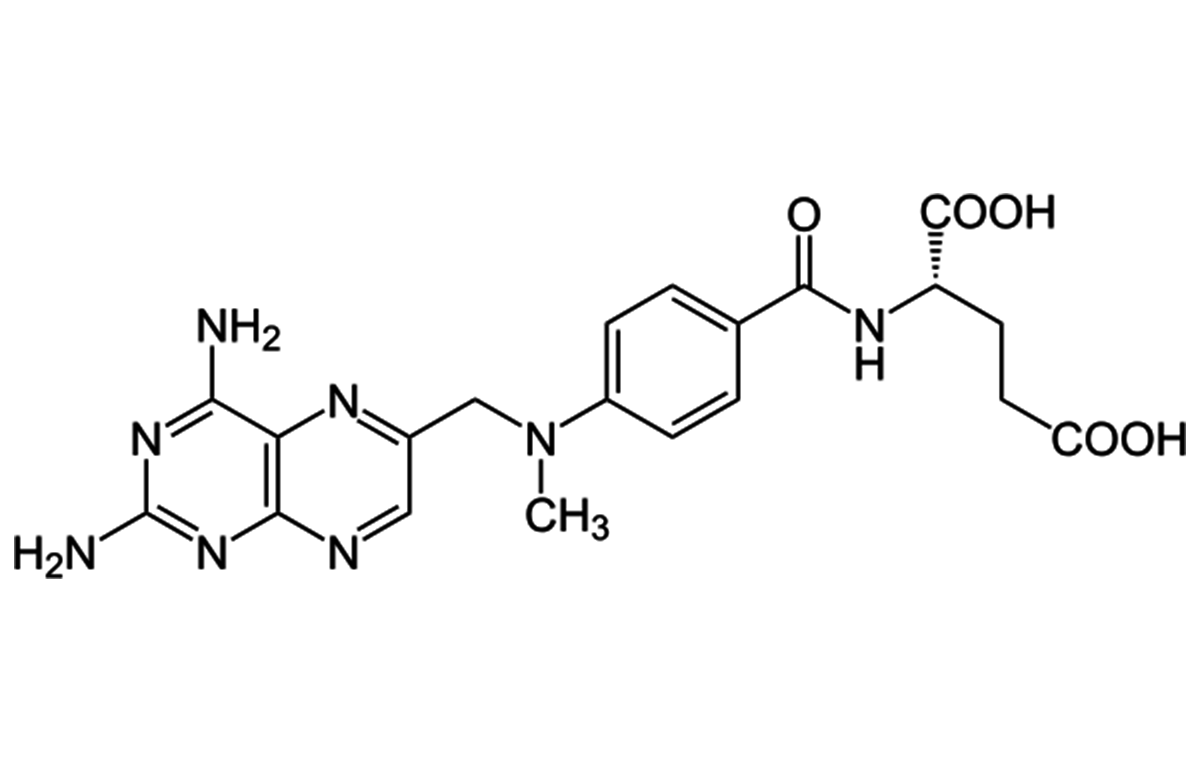

- Leading manufacturer of key anti-cancer APIs.

We continue our focus to bring innovation in Fermentation technologies, Liposomal drug delivery technologies, Lipid based drug delivery technologies, Nanoparticle drug delivery technologies, Synthetic chemistry & High potent cytotoxic products.